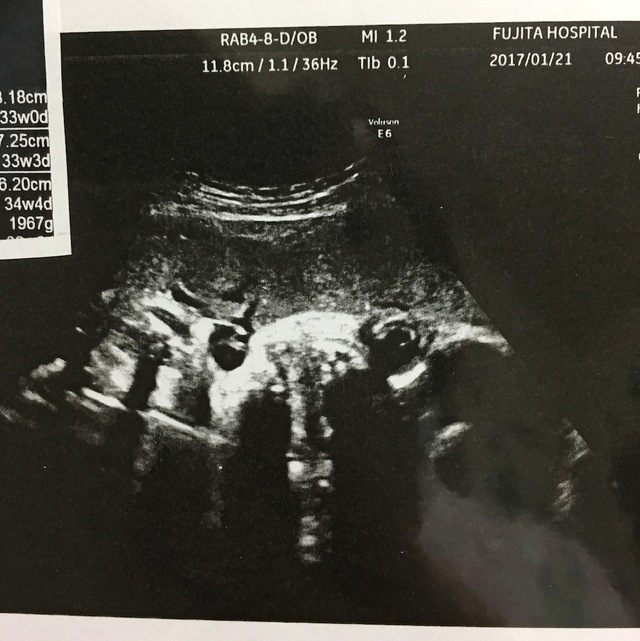

33週0日(33w0d・男の子)|Toriasa さん(31歳)

エコー写真撮影時のエピソード:

里帰り先の病院での初めてのエコー写真です。エコーを当てた瞬間、でっかい我が子の顔が!(笑) ちょっと怖さも感じましたが、まん丸な目がだんだんとかわいらしく感じました。

口もぷっくりしていて、よく動いていました。 子宮の壁をチューチュー吸うしぐさが見えたり、舌を出してペロペロしてるとこが見えてとってもかわいかったです。